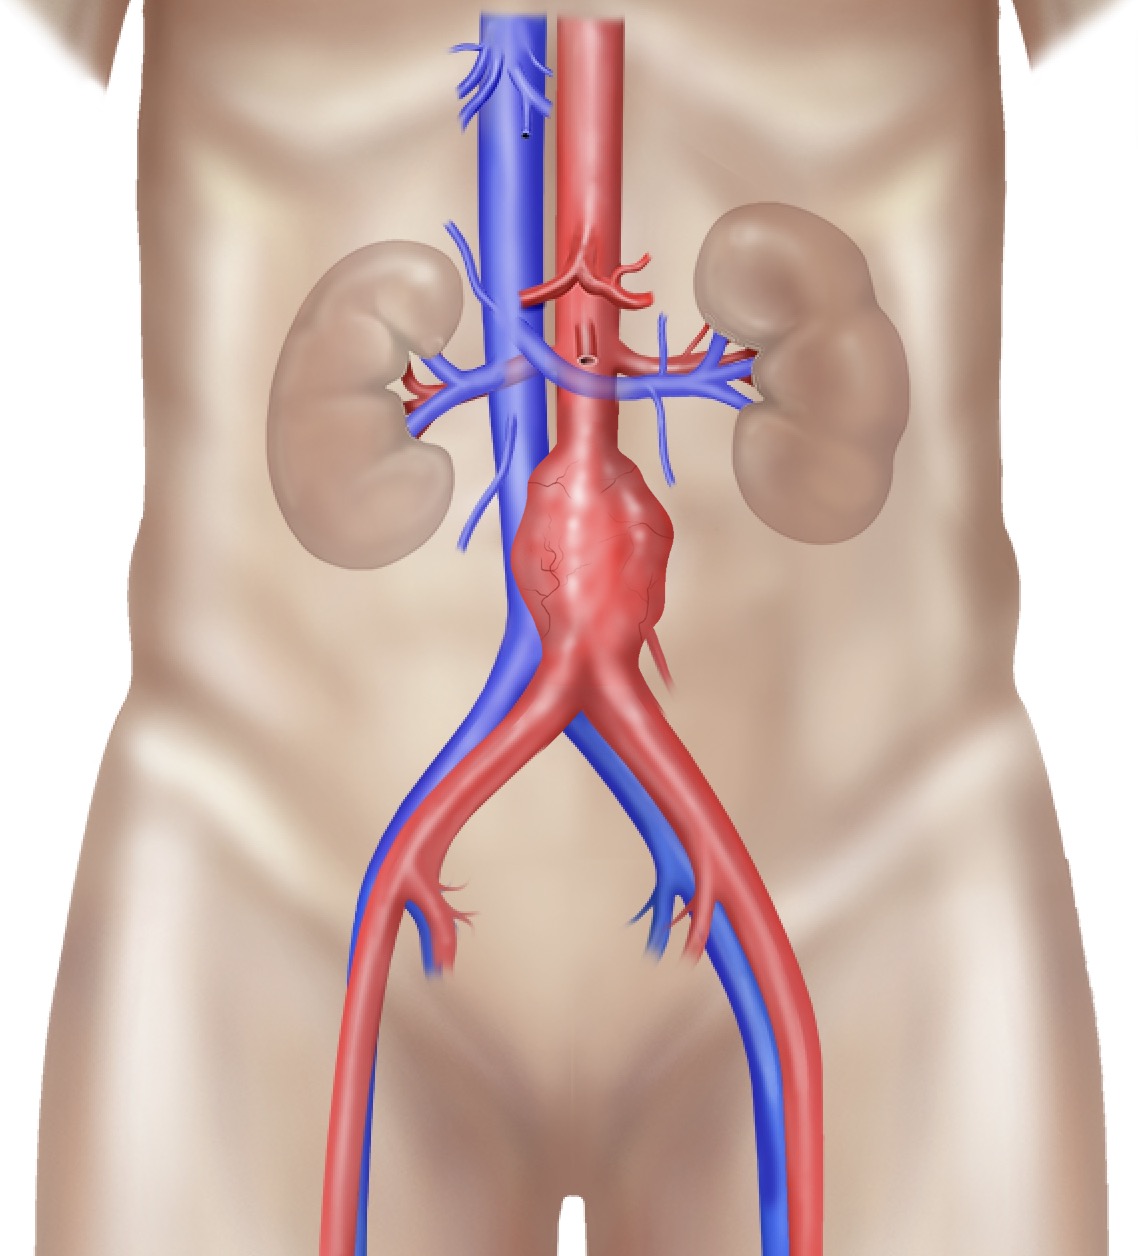

The aorta is the body's largest artery. It carries blood from your heart, down through your chest and abdomen, then splits low down into two branches (the iliac arteries) that supply each leg.

Abdominal aortic aneurysm

An abdominal aortic aneurysm (AAA) is a weak, bulging section of the aorta in your abdomen – a little like a balloon. A normal aorta is about 20 mm wide; it is called an aneurysm once it reaches 30 mm (3 cm) or more.

An aneurysm can also shed small clots that block arteries further down, causing pain or, rarely, loss of a limb.